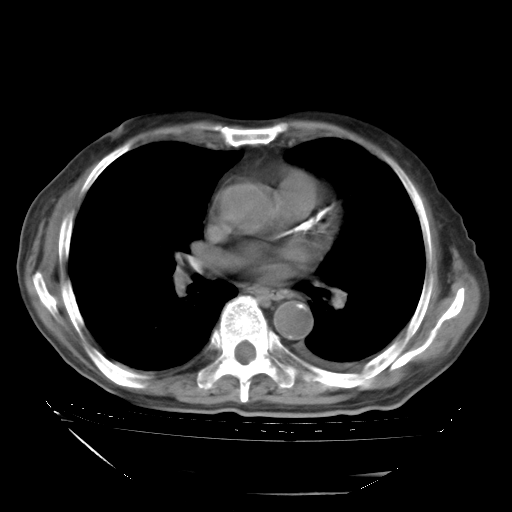

甲强龙80mg/日+抗结核治疗(异烟肼+利福霉素+乙胺丁醇)10天。复查肺部CT。

治疗10天肺部CT

补充下:5月9日胸部CT:似乎已见双下肺胸腔积液了,鉴于目前有下肢水肿,肝功示:白蛋白低,应注意多浆膜腔积液(漏出液可能大?),需注意!